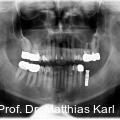

Parallel zur Entwicklung verkürzter Behandlungskonzepte haben sich auch die Außengeometrien zahnärztlicher Implantate hin zu aggressiveren Gewindeformen und konischen Grundkörpern entwickelt. Fotos: © Prof. Dr. Matthias Karl